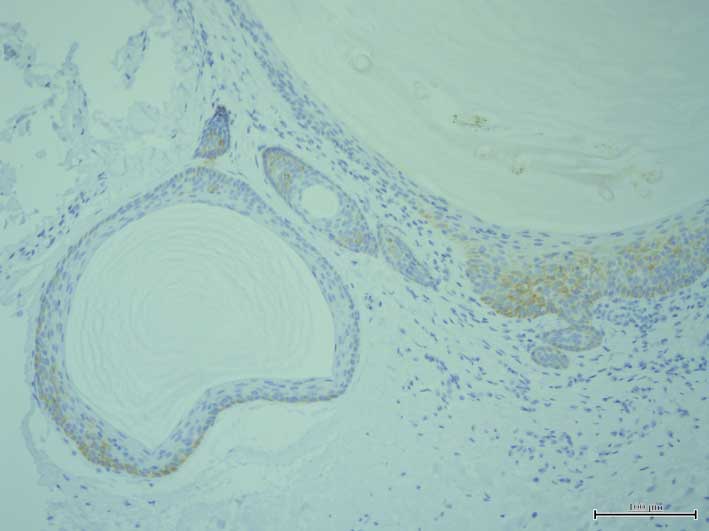

K15 was expressed in the outermost layer of the deeper section of the cyst walls and hair germ structure (original magnification, ×20).

On immunohistochemical examination for keratin and filaggrin expression, the labeled streptavidin-biotin (LSAB) method was used (Dako North America, Inc., Carpinteria, CA, USA). The following mouse anti-human keratin antibodies were used in the present study: 34βB4 (anti-K1; dilution 1:50), LP5K (anti-K7; dilution 1:10), LP3K (anti-K8; dilution 1:50), HP1 (anti-K10; dilution 1:50), LL002 (anti-K14; dilution 1:200), LHK15 (anti-K15; dilution 1:40), LL025 (anti-K16; dilution 1:20), E3 (anti-K17; dilution 1:25), 5D3 (anti-K18; dilution 1:20), b170 (anti-K19; dilution 1:100), Ks 20.8 (anti-K20; dilution 1:25), and 15C10 (anti-filaggrin; dilution 1:50), all from Novocastra Laboratories Ltd. (New castle upon Tyne, UK). The LSAB method was applied according to the manufacturer's protocol. The levels of keratin expression were assessed using anti-keratin antibodies against K1, K7, K8, K10, K14, K15, K16, K17, K18, K19, K20 and filaggrin. K1 (Fig. 2) and K10 expression was detected in the suprabasal layers of the more superficial section of the cyst walls and their expression was attenuated in the deeper sections. By contrast, K14 expression was observed in all layers of the cyst walls (Fig. 3). Notably, K15 was expressed in the outermost layer of the deeper area of the cyst walls and hair germ structures (Fig. 4), while K17 was expressed in all layers of the cyst walls (Fig. 5). The expression of other keratins was not detected in the cyst walls. Filaggrin was expressed in the superficial layer of the more superficial sections of the cyst walls (Fig. 6). The milia were treated with adapalene. However, no remarkable change was observed and the treatment was discontinued.